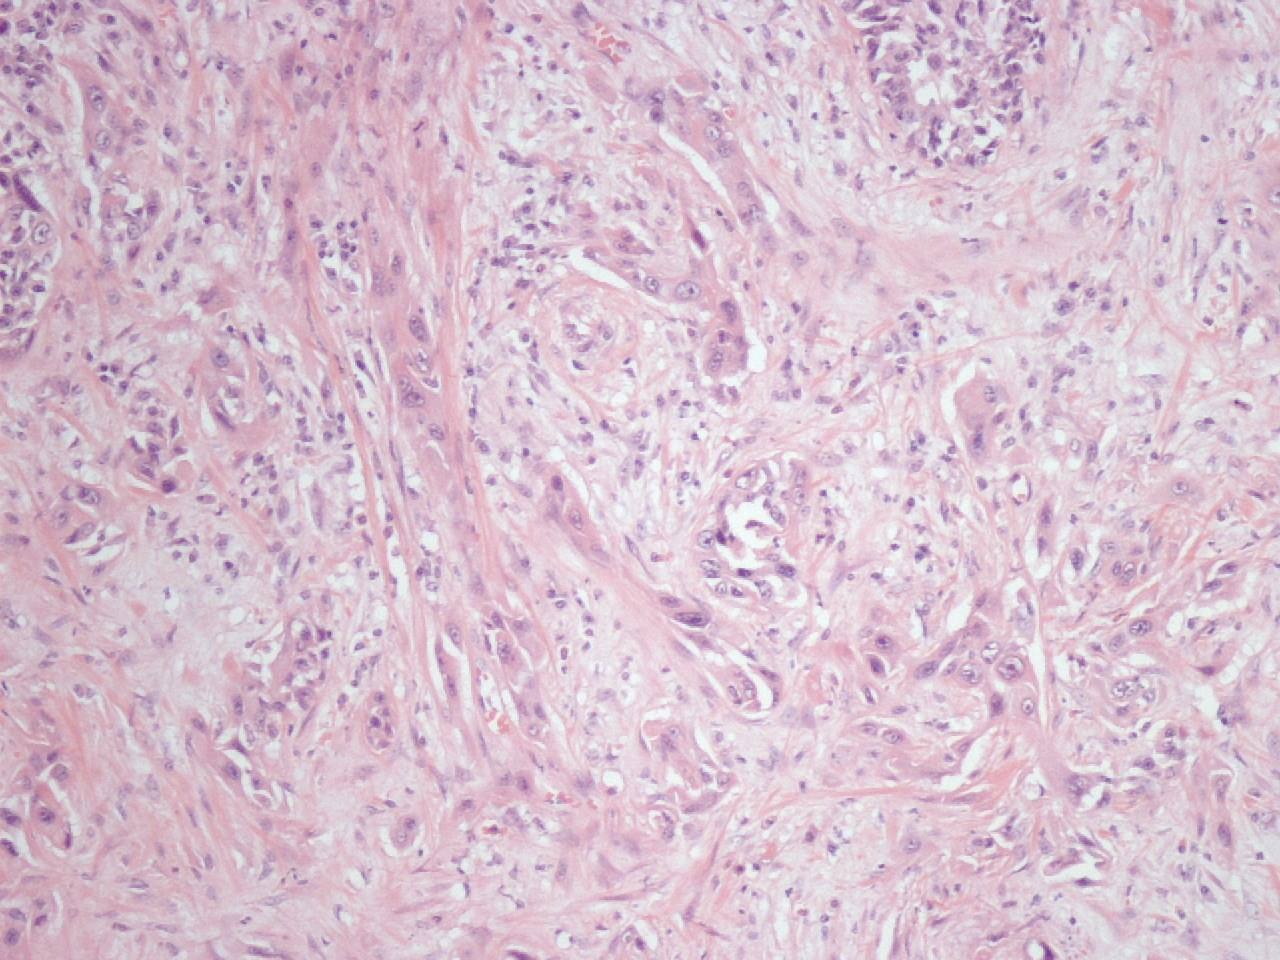

Classification of renal tumors

Case ID: 1270